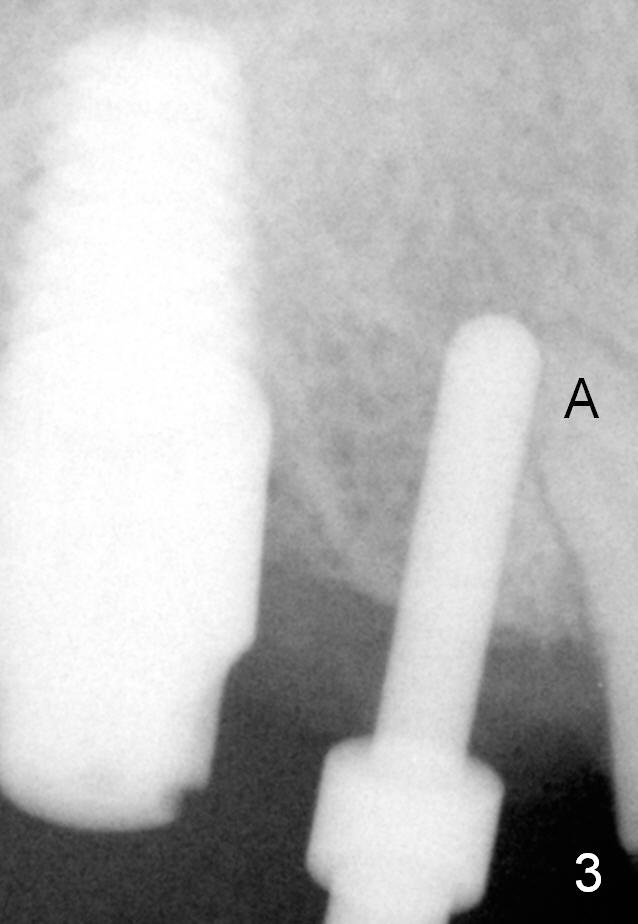

The implant at the site of #3 is intentionally placed distal as part of a plan to distalize the teeth #4-6 (Fig.1). Ortho started, but the patient did not want to pursue it. The most efficient way to terminate it is to dislodge every one of brackets/bands. When it is time for restoration for implants at the sites of #3 and 30, it is a challenge to deal with the space mesial to #3. The patient is planning to leave the country in 20 days. Fortunately he agrees to have an extra implant (Fig.2). It must be small in diameter. The initial osteotomy does not go on smoothly, approaching the apex of the tooth #4 (Fig.3 A). The osteotomy is moved distally and the trajectory is changed. It appears to be overcorrected (Fig.4). After re-adjustment, a 3.5x14 mm implant is placed with insertion torque between 15 and 20 Ncm (Fig.5). An abutment is placed with perio dressing applied around it as well as #3 after suturing. When the wound heals and before the patient leaves the country, the abutment is removed.